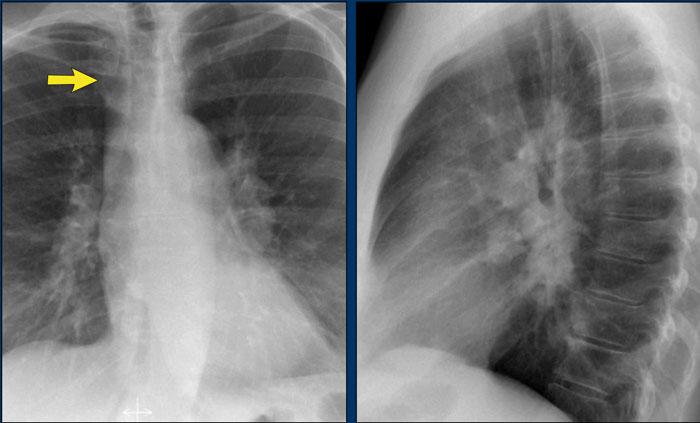

Ví dụ Lâm sàng: Dấu hiệu Kín đáo của Suy tim Sung huyết

Hãy bắt đầu bằng cách xem xét các phim X-quang ngực hiện tại.

Chỉ dựa trên các hình ảnh này, người đọc có thể nghi ngờ suy tim sung huyết (CHF), mặc dù các dấu hiệu còn khá kín đáo.

Bây giờ hãy xem lại phim cũ trước đó…

Việc cuộn qua lại giữa phim hiện tại và phim cũ giúp tăng đáng kể độ tin cậy trong chẩn đoán suy tim sung huyết.

Các dấu hiệu so sánh chính bao gồm:

- Kích thước tim: Tăng nhẹ so với phim trước; tuy nhiên, tim to đã hiện diện từ trước.

- Hệ mạch máu phổi: Cương tụ mạch máu nhẹ gợi ý tăng áp lực tĩnh mạch phổi.

- Hình ảnh mô kẽ: Dấu hiệu kín đáo của phù mô kẽ.

- Tràn dịch màng phổi: Tràn dịch lượng ít hai bên, với thay đổi kín đáo ở bờ dưới-sau của các thùy dưới, gợi ý tích tụ dịch.